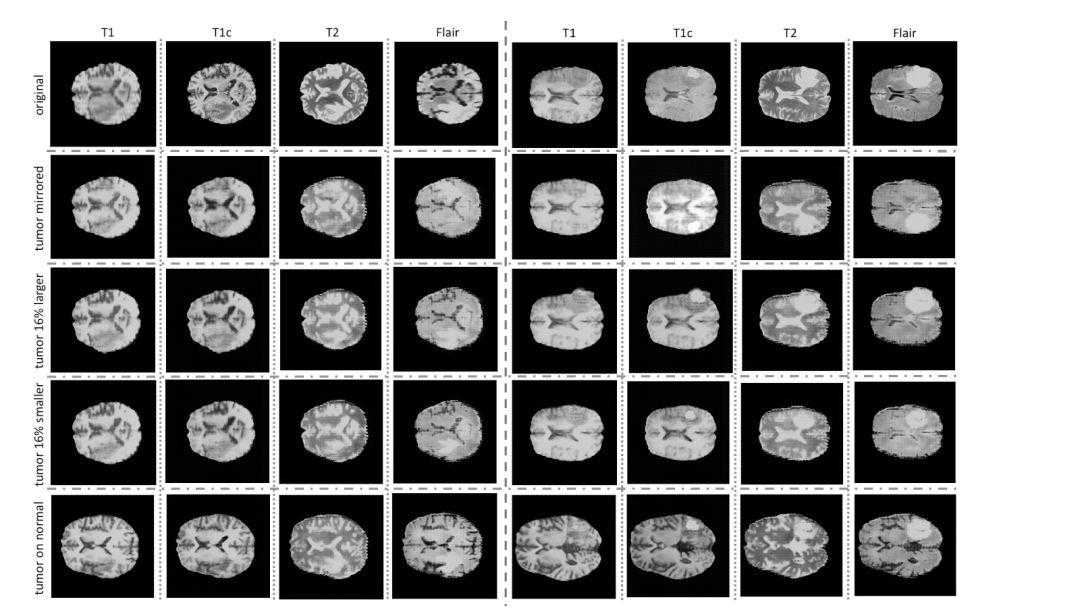

深度学习同时还可以帮助研究人员积累数量可观的数据,并在应用研究上实现突破。一系列研究已经开始利用生成对抗网络来生成一系列脑部异常核磁共振图像,用于训练医学图像分析神经网络,实现前沿医学领域的研究。

这些合成数据可以解决深度学习在医学领域面对的数据不均衡、以及缺乏可靠数据源的困难。